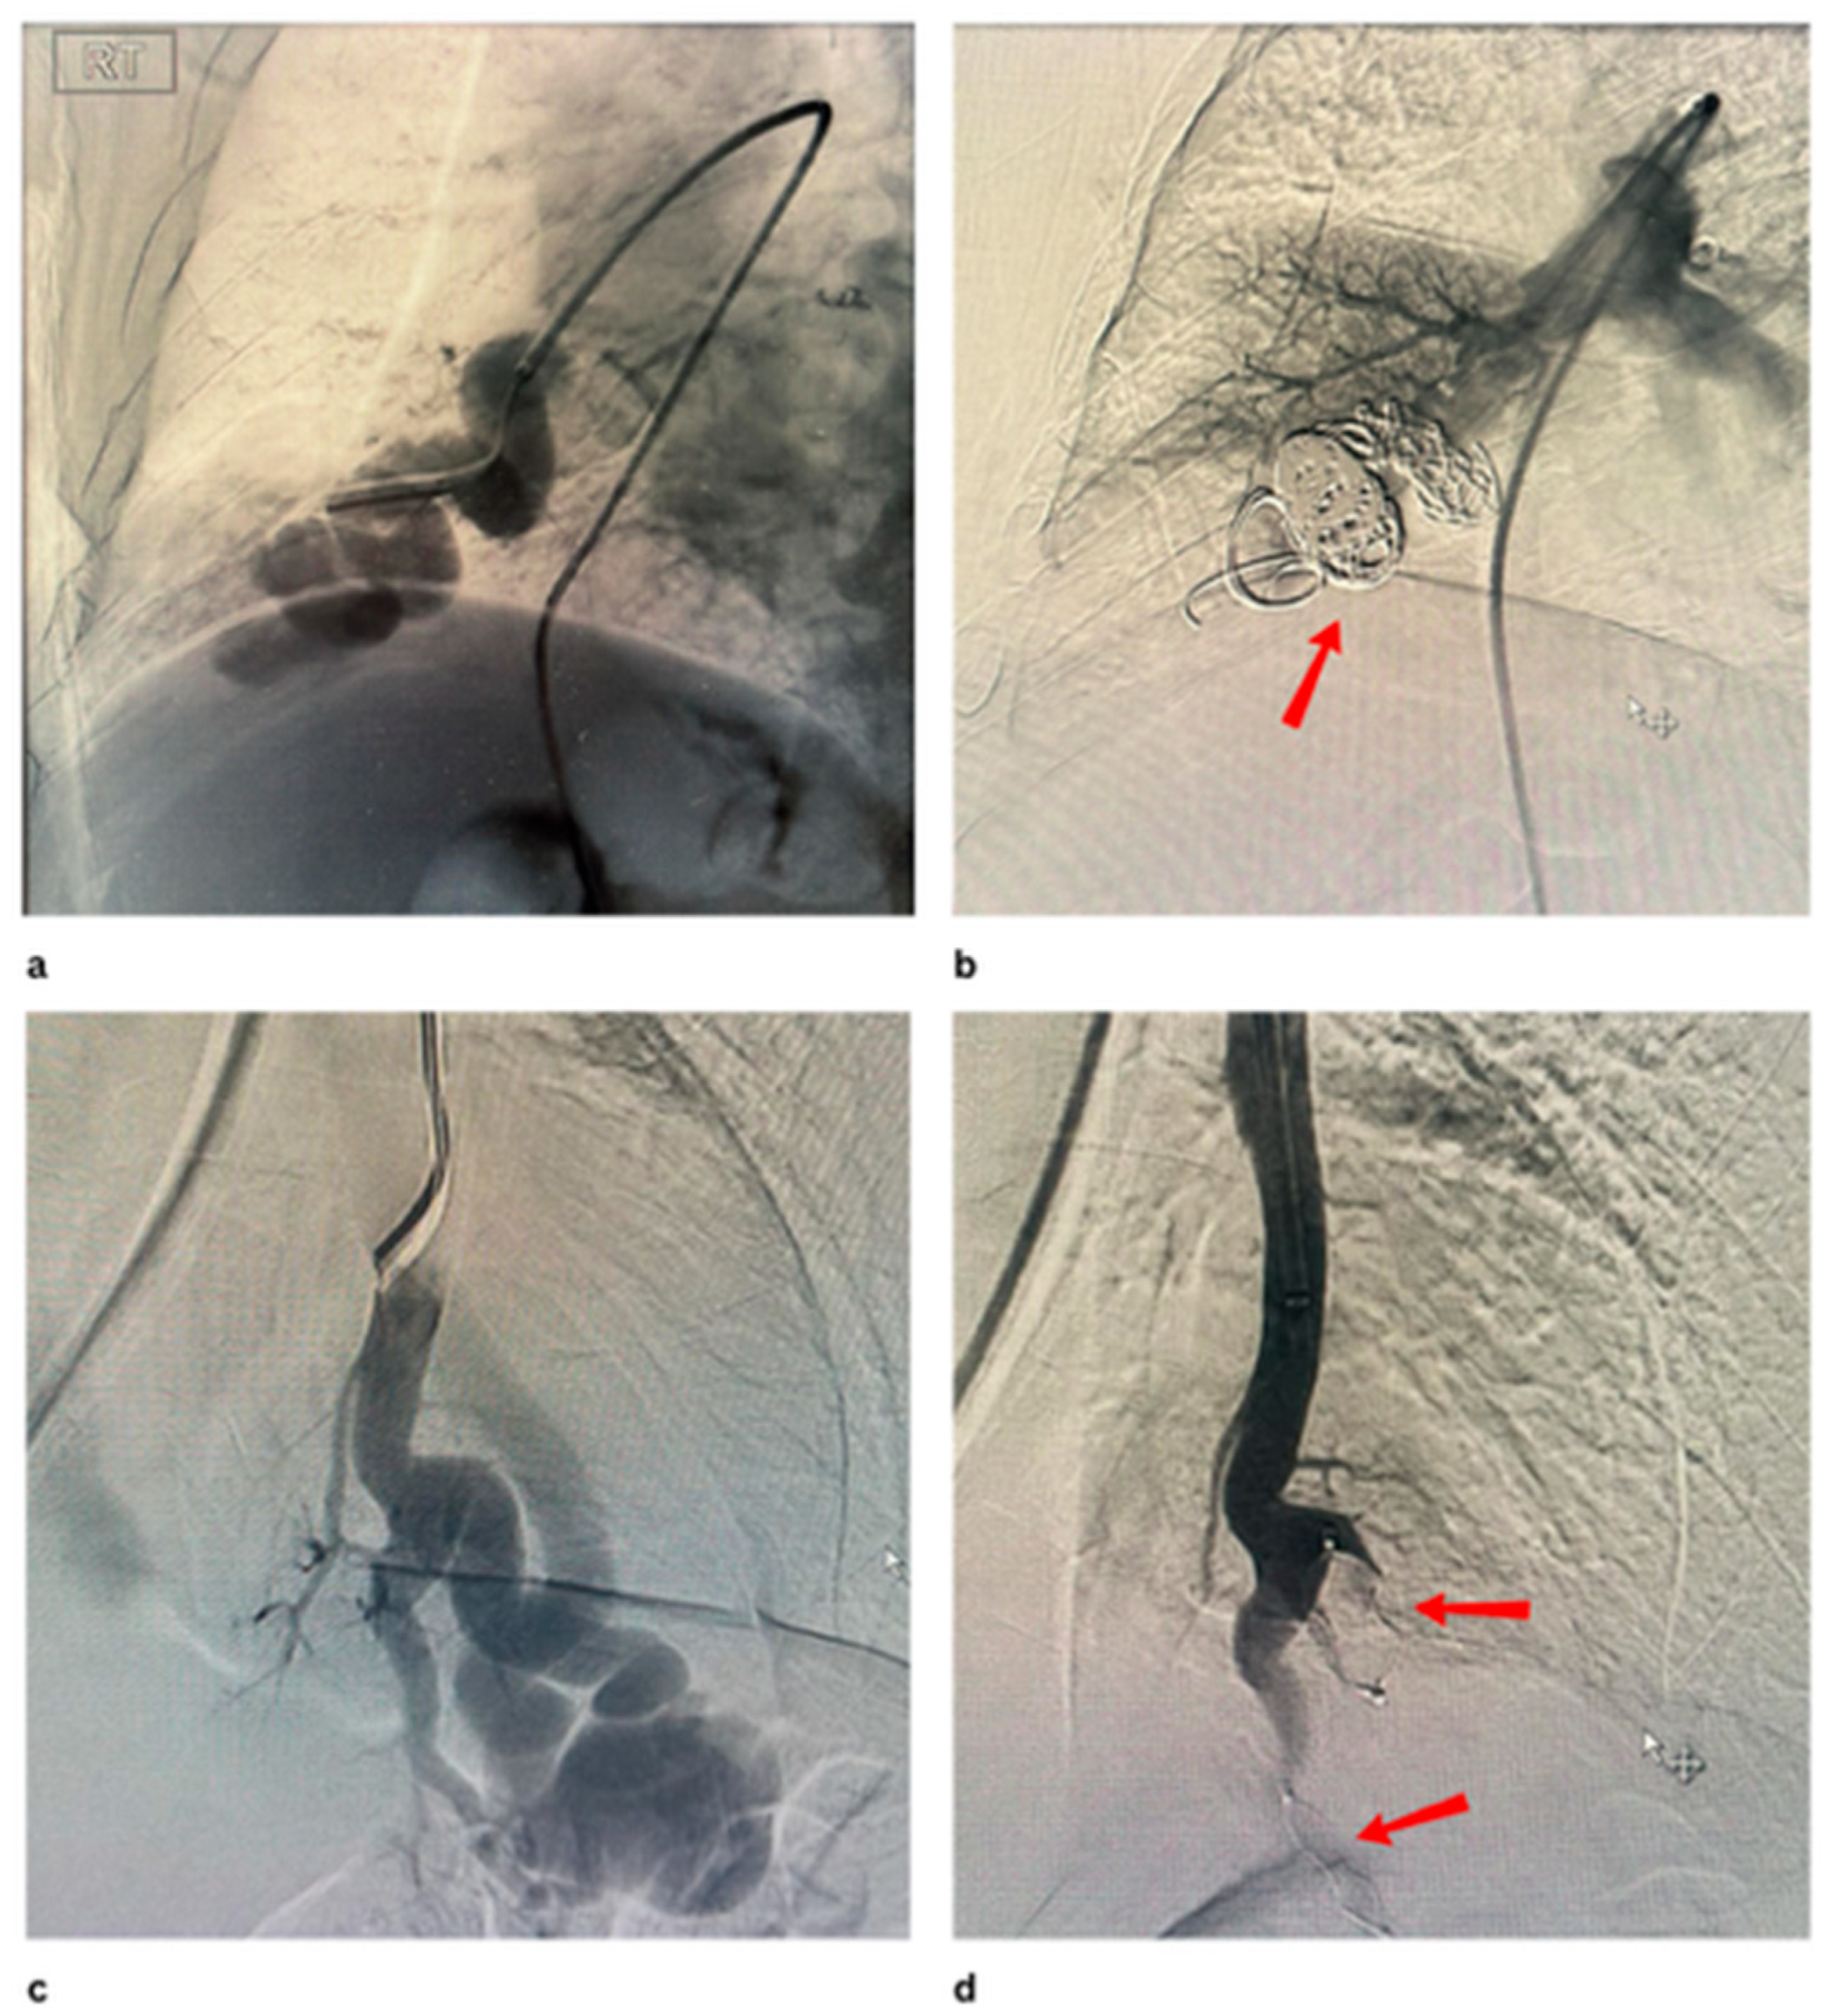

- Kanematsu, M.; Kondo, H.; Goshima, S.; Tsuge, Y.; Watanabe, H.; Moriyama, N. Giant High-Flow Type Pulmonary Arteriovenous Malformation: Coil Embolization with Flow Control by Balloon Occlusion and an Anchored Detachable Coil. Korean J. Radiol. 2012, 13, 111–114. [Google Scholar] [CrossRef][Green Version]

- Cil, B.E.; Erdogan, C.; Akmangit, I.; Cekirge, S.; Balkanci, F. Use of the TriSpan Coil to Facilitate the Transcatheter Occlusion of Pulmonary Arteriovenous Malformation. Cardiovasc. Interv. Radiol. 2004, 27, 655–658. [Google Scholar] [CrossRef] [PubMed]

- Mori, K.; Shiigai, M.; Saida, T.; Anno, I.; Wada, M.; Minami, M. A Modified Metallic Coil Embolization Technique for Pulmonary Arteriovenous Malformations Using Coil Anchors and Occlusion Balloon Catheters. Cardiovasc. Interv. Radiol. 2008, 31, 638–642. [Google Scholar] [CrossRef]